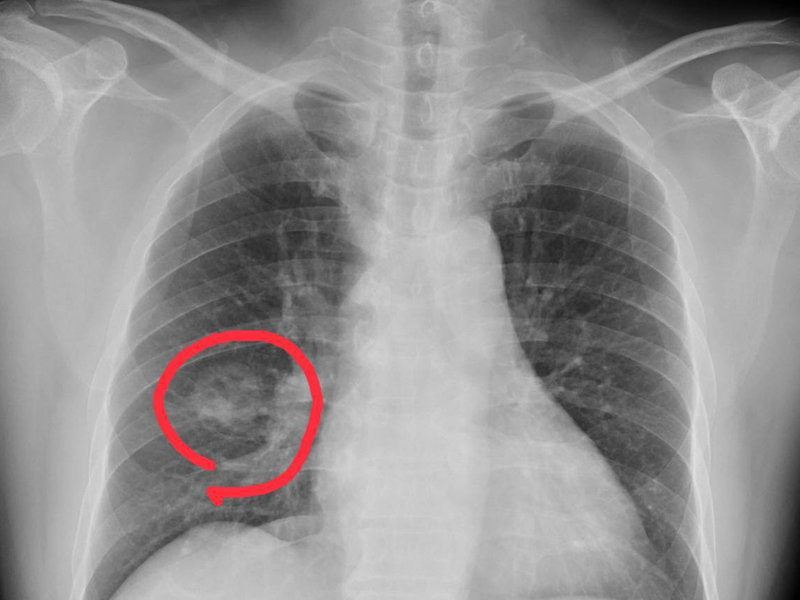

腸息肉初期沒有明顯癥狀,只能通過體檢篩查發現。發現息肉后,醫生會根據其大小、形態、病理結果類型來決定治療方式。

一般來說,帶蒂、直徑小於2厘米、表面光滑、活動度好的息肉是良性的;

黏膜下扁平、直徑大於2厘米、表面有出血或潰瘍的,往往提示息肉惡變。

從鏡下形態看

邊緣平坦、光滑、圓潤的息肉,通常是良性,若小於等於5毫米,可以隨訪觀察。

如果外觀粗糙,有凹陷、扁平、潰瘍、出血或壞死、星芒狀開口,惡性病變的可能性很大,一定要切除。